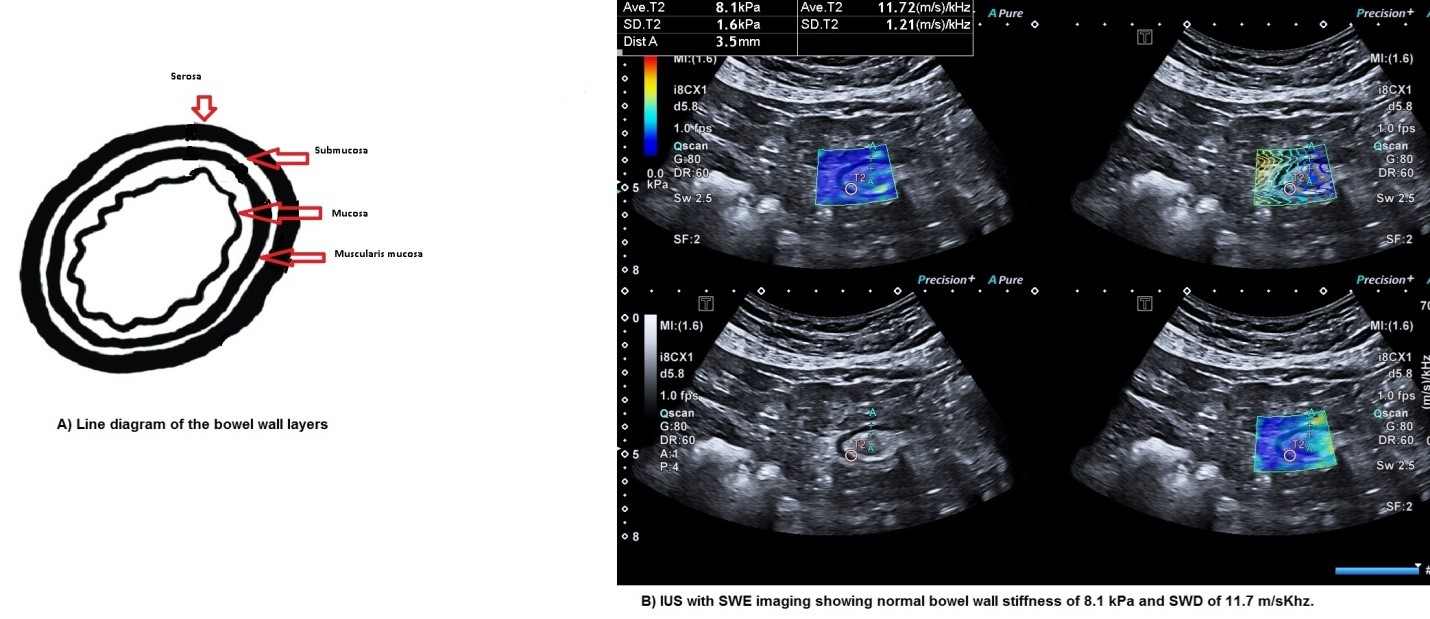

Evaluation of chronic pediatric diarrhea is more challenging and various algorithms have been suggested based on history and a combination of multiple blood, stool, and various allergy tests along with invasive endo - colonoscopies and biopsies [3,4]. Traditionally grey scale ultrasonography has been used to evaluate small bowel. Using high-frequency transducers with a graded compression technique the different layers of the bowel can be distinctly visualized (Figure 1A) along with wall thickness measurement and the condition of surrounding mesentery, lymph nodes, and peritoneal fluid. It has 100% sensitivity and specificity to rule out intestinal intussusception and has a high sensitivity for appendicitis. USG has a limited specificity in determining the cause of inflammatory bowel disease and also in the detection of acute bowel inflammation.

Figure 1. A. Line diagram of bowel wall layers. B. IUS with SWE imaging showing normal bowel wall stiffness of 8.1 kPa and SWD of 11.7 m/sKhz.

Recent advances in imaging i.e. shear wave elastography (SWE) have opened up newer applications of SWE to evaluate small bowel in patients with both acute and chronic diarrhea. The technique involves the generation of shear waves using ultrasound with the same transducer and causes displacement of the soft tissues in the region of interest. The speed of these waves is calculated, and the stiffness is determined in kilopascals. Recently a new parameter of shear wave dispersion (SWD) has also been added which measures the viscosity of the tissues and is an indirect imaging marker of inflammation (Figure 1B).